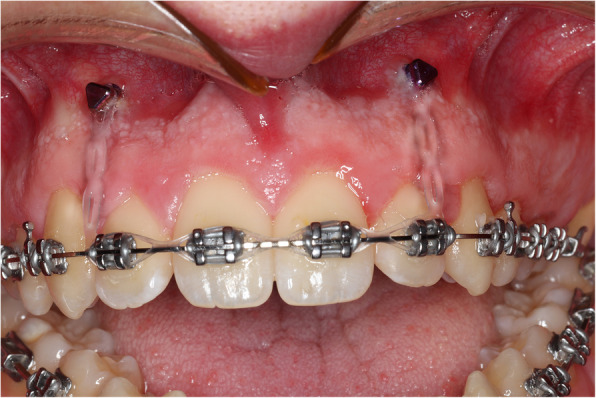

Case presentation: A 19-year-old male white Caucasian patient presented with a clinically significant anterior open bite of predominantly skeletal aetiology. The objective of preoperative levelling in the maxillary dental arch was to avoid any extrusion of the anterior dentition. To achieve this aim, two temporary anchorage devices (TADs) were placed in the maxillary alveolar bone, and relatively passive elastic force was applied from the archwire to the TADs in order to prevent maxillary incisor extrusion during arch levelling. This elastomeric chain was maintained throughout the alignment and levelling of the maxillary dental arch. The patient had a Le Fort I osteotomy of the maxilla with differential posterior impaction and advancement, and mandibular forward autorotation and small setback of the mandibular body with bilateral sagittal split osteotomy, to achieve a Class I incisor and skeletal position. No vertical movement of the teeth was carried out or required following surgery. The patient was debonded 3 months following surgery and fitted with removable retainers. Cephalometric superimpositions demonstrated that no extrusion of the anterior maxillary dentition occurred, which is the main parameter to improve postoperative stability of the anterior open bite correction.